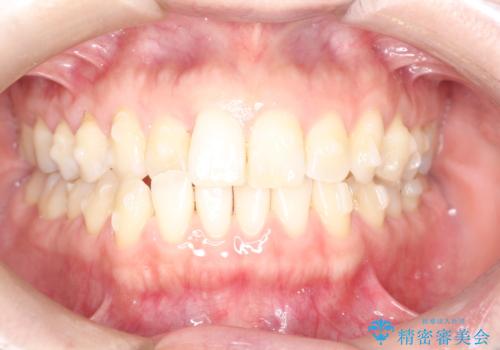

上の歯と下の歯が反対にかんでいる インビザラインによる目立たない矯正

- 右上の前から2番目と3番目の歯が内側に引っ込んでしまっているのを主訴に来院されました。

右上の2番目と3番目のはが前後反対にかんでしまっている状態でした。

内側に引っ込んでいる歯も、インビザラインにてしっかり外側に動かすことができます。